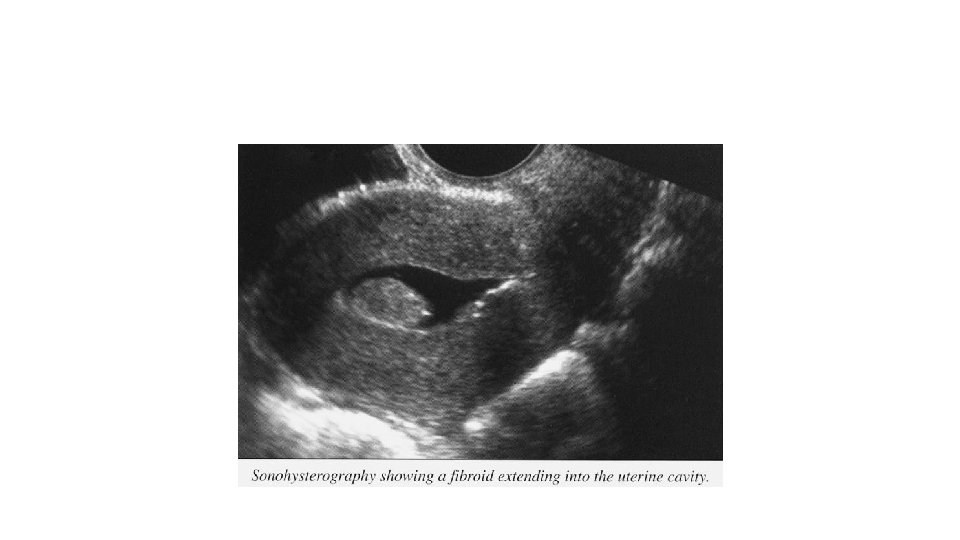

Salin sonohisterografi (SİS) • Kavite içine salin verildikten sonra USG ile değerlendirilmesidir. • Submukozal myom, polip tanısında duyarlılığı yüksektir. • Yüksek PPD(%90) sahiptir • İntrakaviter lezyonlar için histeroskopi kadar güvenilir.